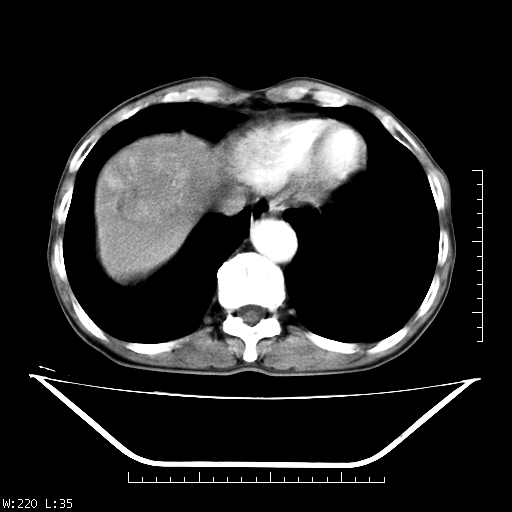

男,70,右上腹痛两月,有乙肝病史,b超提示肝占位,ct如下,请会诊。

补充:该患者afp9.24

肝右叶类圆型密度减低影,密度不均,边界清晰其内可见更低密度影,腹膜后可见小淋巴结肿大,增强扫描动脉期病灶明显强化,静脉期及延时扫描见强化不明显,快进快出表现。

1.肝右叶低密度影考虑为肝癌;

2.肝转移待除外。

平扫呈低密度占位,动脉期斑片状明显强化,病灶边缘清晰,见假包膜;门脉期呈低密度,符合肝癌快进快出强化特征

补充:该患者afp 9.24,似乎与原发性肝癌不符合,另胰头区结构正常吗?请大家继续发表高见。